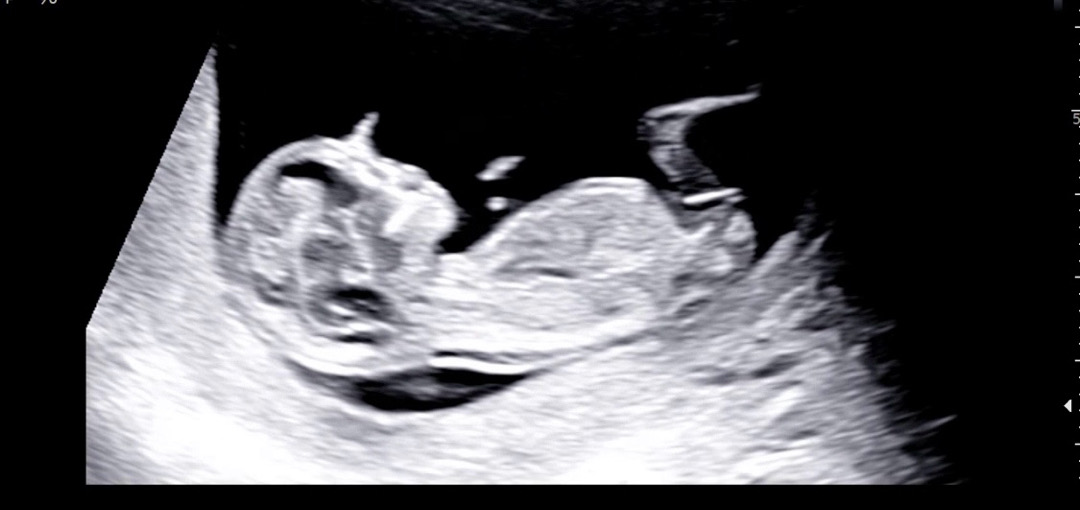

오늘12주3일차! 드디어 1차 기형아 검사 하고왔어요 다행히 기본적인 것들은 정상이라고해서 한시름 놓여요 ㅠㅠ 제가 걱정인형이라서 걱정을 많이 했거든요 밥먹고 초코우유 마시고 가서 그런지 처음으로 움직이는 모습을 보게 되어서 행복했답니다 아직까지도 내안에 있다는게 넘 신기해용 아직 이르지만 혹시 고수님들 이 사진으로 딸인지 아들인지 예측 할수 있을까요???!🩷

저도 딸에 한표요!

왠지 딸같아요ㅎㅎ